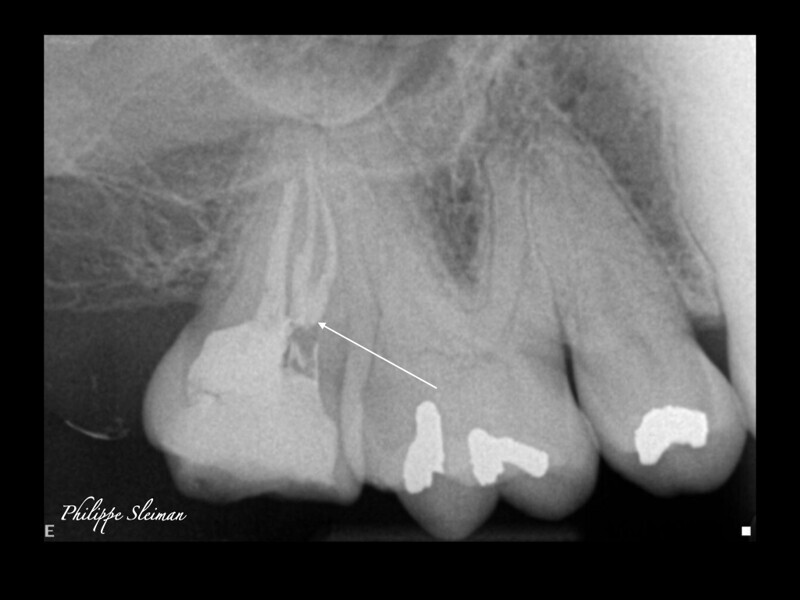

Clinical management of maxillary second molar root canal therapy in different anatomical situations